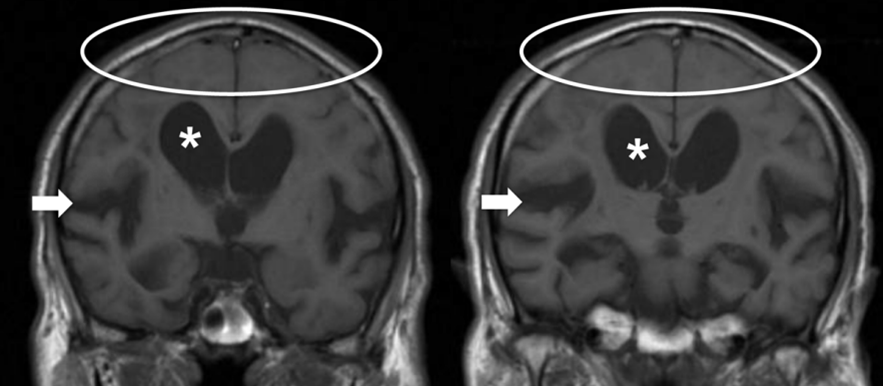

脑 MRI特征:脑室扩大(如 Evans 指数 > 0.3);胼胝体角缩小;DESH征(脑室扩大伴蛛网膜下腔不成比例扩大),见图2。DESH 是 CSF 动力学障碍的表现,与术后良好预后相关。脑MRI可以排除脑积水、脑萎缩、白质病变等。颈椎/腰椎MRI可排除脊髓或神经根压迫。

图2:HS在MRI上的典型表现:冠状位T1加权像冠状层面,显示脑室扩大(*)、高凸面(顶部)及中线区域蛛网膜下腔呈现“狭窄、紧凑”的状态(椭圆圈),以及外侧裂扩张(箭头)(图源:参考文献[4])